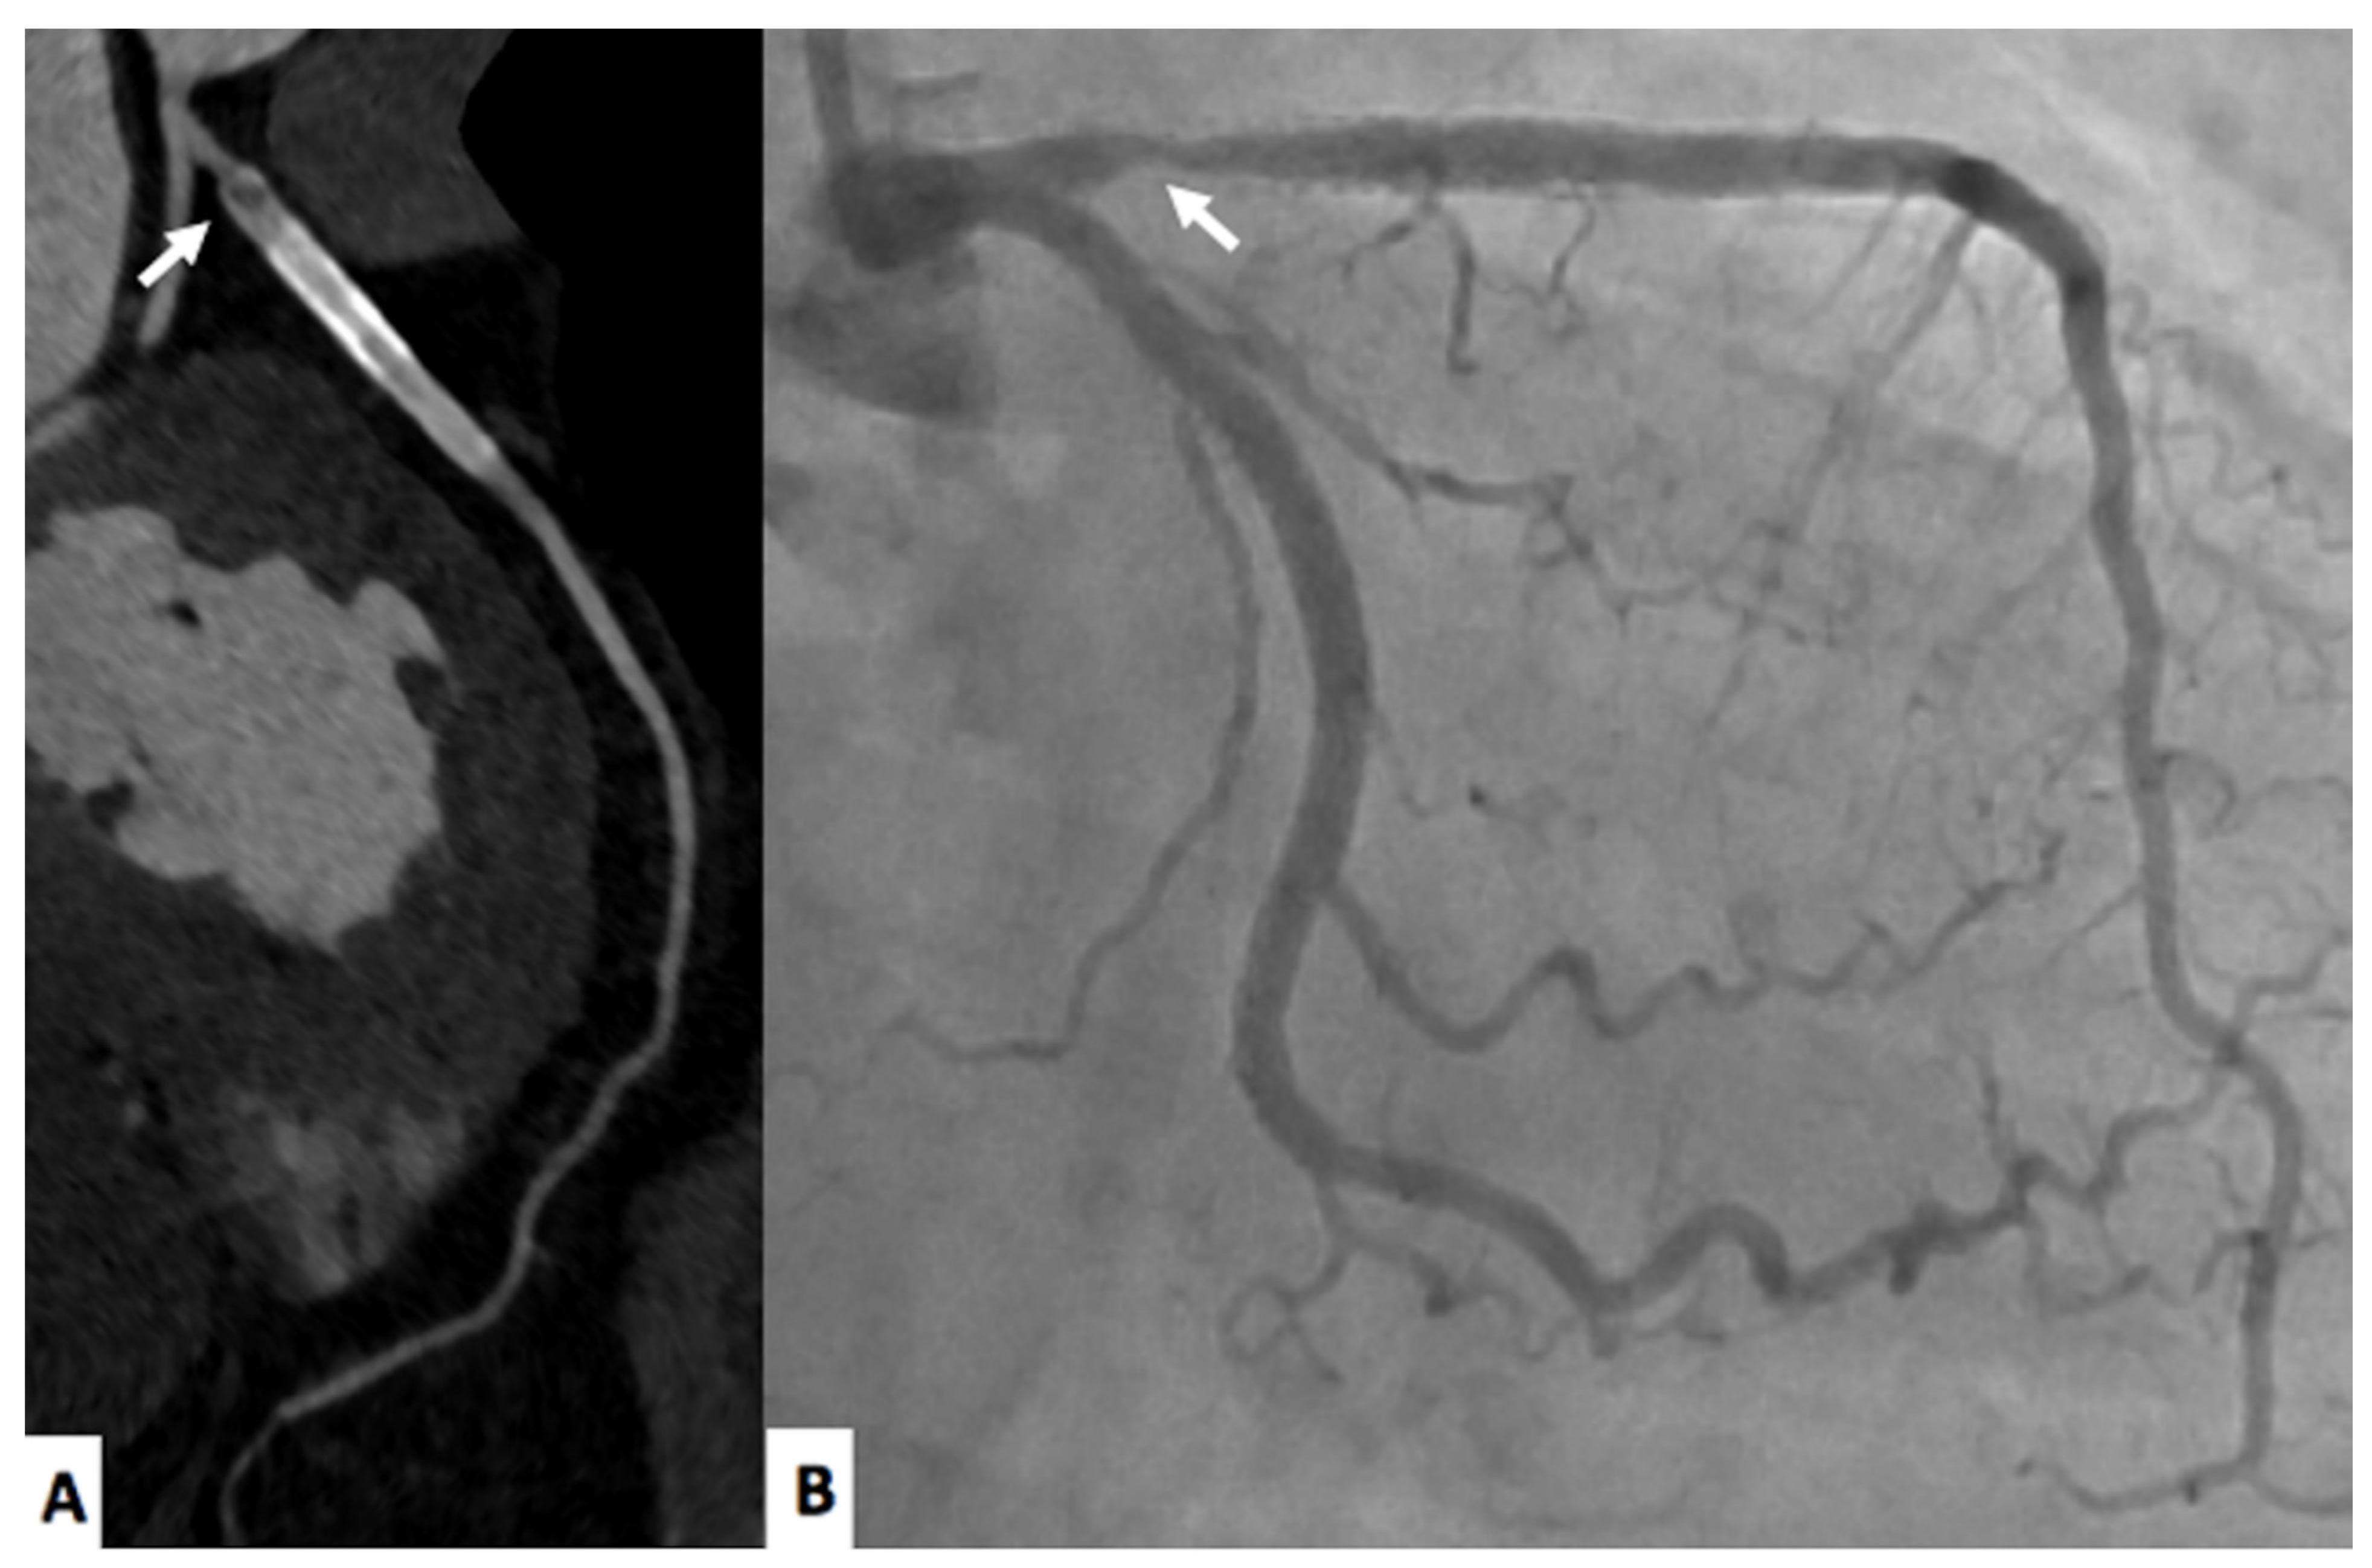

2.1. Coronary Computed Tomography Angiography

2.2. FFRct and CTP